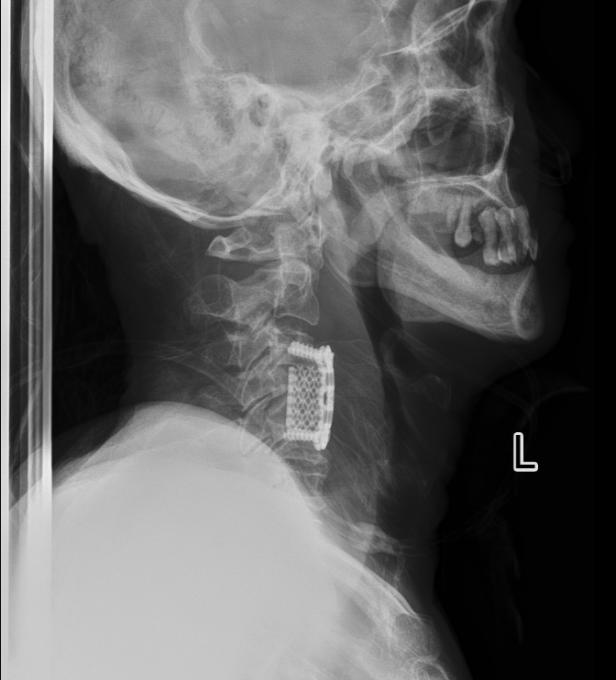

术后患者脊髓压迫解除,脊柱稳定性建立,在此基础上,专科化术后护理对巩固疗效、促进神经恢复、防范并发症同样至关重要。

4.5  患者术后影像